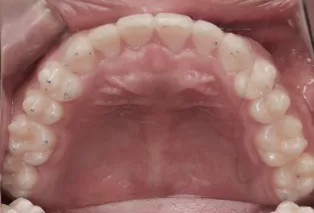

Photos intra-orales